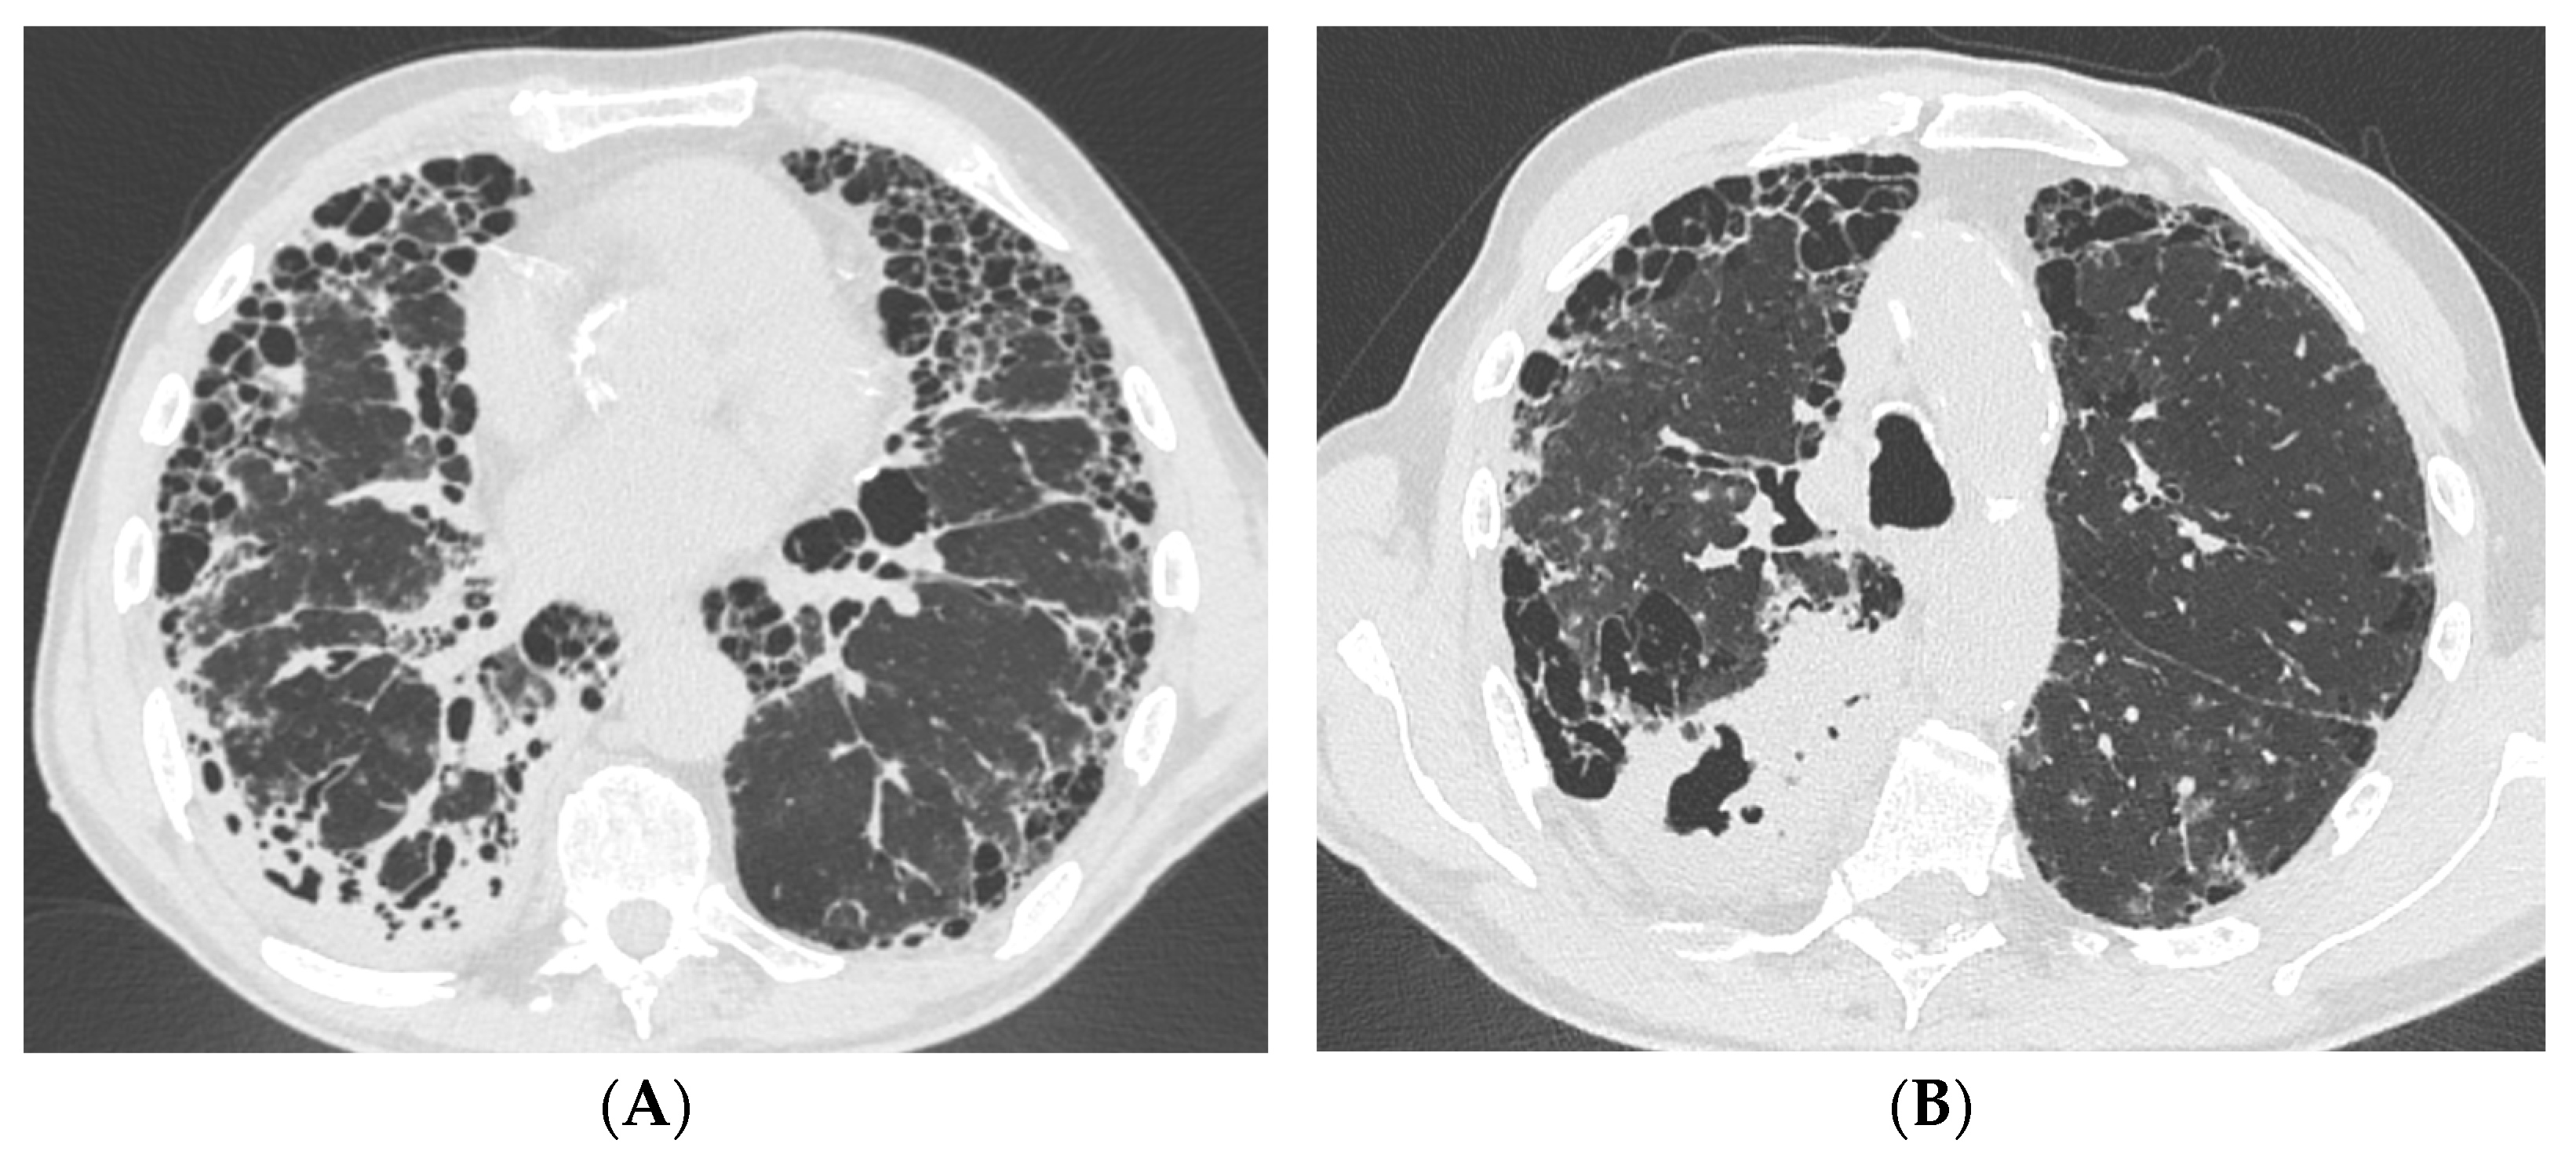

A 76-year-old male, a former smoker, with a three-year history of connective tissue disease-associated interstitial lung disease (CTD-ILD) classified as rheumatoid arthritis (RA) with a UIP at chest HRCT, as adjudicated by multidisciplinary discussion (MDD), managed with azathioprine and long-term oxygen therapy, was referred to the Emergency Department with massive hemoptysis. Upon admission to the emergency department, the patient presented with hypoxemic hypercapnic respiratory failure that required oxygen therapy via Venturi mask with a fraction of inhaled oxygen (FiO2) equal to 40%. Laboratory tests revealed significantly elevated inflammatory markers and anemia, with a hemoglobin level equal to 8 g/dL, necessitating a transfusion of two units of packed red cells. Therefore, an urgent contrast-enhanced chest CT scan was performed; it demonstrated the presence of UIP pattern and bilateral cavitary lung consolidations, of which the most extensive was located in the right lower lobe (Figure 1). Conversely, no active sources of bleeding were identified. Following hemodynamic stabilization, a bronchoscopy with bronchoalveolar lavage (BAL) was performed to further evaluate the pulmonary findings at chest HRCT; while endobronchial blood clots were removed, no active signs of bleeding were observed. Then, the patient was administered broad-spectrum empirical antibiotic therapy with piperacillin-tazobactam and vancomycin, despite the absence of microbiological results. The bacterioscopic assessment of the BAL fluid tested positive for acid-fast bacilli, while the polymerase chain reaction (PCR) for Mycobacterium tuberculosis (Mtb) was negative. Additionally, PCR testing confirmed the presence of Mycobacterium kansasii, which was further confirmed by microbiological culture. The administration of antibiotic therapy improved clinical status and gas exchange by reducing FiO2 from 40% to 24%. The patient started a targeted antimicrobial therapy with rifampin, azithromycin, and ethambutol, which was well-tolerated, leading to the patient’s discharge with oxygen supplementation only during physical exertion. Symptoms such as persistent catarrhal cough, hemoptysis, low-grade fever, and weight loss gradually resolved after six months of therapy. Hence, the case underwent a second MDD, and although criteria for progressive pulmonary fibrosis (PPF) were identified, antifibrotic therapy with nintedanib was not initiated due to the higher risk of iatrogenic hepatitis associated with concomitant rifampin use. Eventually, antifibrotic treatment was not initiated and deferred until the completion of antimycobacterial therapy, which lasted 12 months from the date of negative sputum cultures, for a total of 18 months.

Figure 1. Case #1 contrast-enhanced CT scan acquired in the emergency room during massive hemoptysis. UIP pattern is evident in the lower lobes (A), while the most extensive consolidation is located in the apical segment of the right lower lobe (B). Abbreviation: CT, computed-tomography; UIP, usual interstitial pneumonia.

A 82-year-old woman with a history of CTD-ILD secondary to RA and thrombosis of femoral veins was admitted to the Emergency Room for hypoxic–hypercapnic respiratory failure requiring oxygen therapy with FiO2 35% in a febrile state. The patient complained of dyspnea, cough, and weight loss (8 kg) over the previous 3 months. In anamnesis, there was recent close contact with active TB. Laboratory tests revealed elevated inflammatory markers, neutrophilic leukocytosis, moderate anemia, and high D-dimer levels. Chest X-ray showed bilateral reticular diffuse interstitial lung alterations with consolidation in the left upper field. Chest HRCT demonstrated multiple bilateral excavated lesions, parenchymal consolidation with air bronchogram, and a UIP pattern characterized by traction bronchiectasis and reticulation (Figure 2). The patient underwent bronchoscopy with BAL: fluid molecular essay would later result positive for Mtb. Moreover, the mycobacteria growth indicator tube tested positive for TB resistant to isoniazid, rifampin, streptomycin, and pyrazinamide. Therefore, antibiotic therapy with amikacin, amoxicillin/clavulanate, meropenem, clofazimin, cicloserin, bedaquilin, and moxifloxacin was started. During the prolonged hospitalization, the patient received a red blood cell transfusion (two units) for drug-induced anemia. After two months of prescribed antibiotic therapy, a follow-up contrast chest computed tomography (CT) showed the reduction in extension of the excavated lesions and the consolidations and highlighted subsegmental pulmonary embolism. After a cardiological consultation, the patient was finally discharged home with no indication for anticoagulant treatment and no need for oxygen therapy at rest, while maintaining the indication for supplemental oxygen during exertion. The patient died at home the following month, prior to the next scheduled outpatient visit.

Figure 2. Case #2 chest HRCT scans acquired in the emergency room. Multiple bilateral excavated lesions and parenchymal consolidation with air bronchogram are more evident in the upper lobes (A), while the UIP pattern characterized by traction bronchiectasis and reticulation is more prominent in the lower lobes (B). Abbreviations: HRCT, high-resolution computed tomography; UIP, usual interstitial pneumonia.